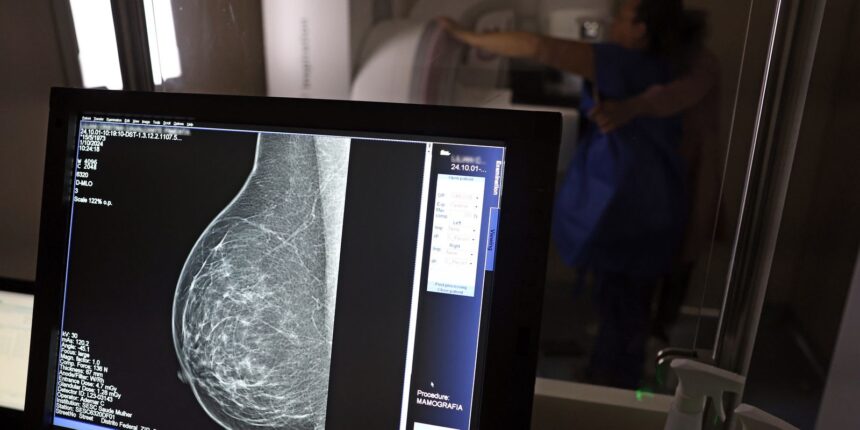

O Ministério da Saúde passou a recomendar o acesso a mamografia, via Sistema Único de Saúde (SUS), para mulheres de 40 a 49 anos – mesmo que não haja sinais ou sintomas de câncer de mama. De acordo com a pasta, a faixa etária concentra 23% dos casos da doença, e a detecção precoce aumenta as chances de cura.![]()

Até então, a orientação era que o exame fosse feito a partir dos 50 anos.

A medida faz parte de um conjunto de ações anunciadas nesta terça-feira (23) voltado para a melhoria do diagnóstico e da assistência. A recomendação para mulheres a partir dos 40 anos é que o exame seja feito sob demanda, em decisão conjunta com o profissional de saúde.

As mamografias via SUS em pacientes com menos de 50 anos, de acordo com a pasta, representam 30% do total, o equivalente a mais de 1 milhão apenas no ano de 2024.